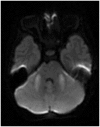

Results: Eight out of the 20 patients included in the study were on cyclosporine or tacrolimus based immunosuppressant therapy for kidney transplant. Four patients had severe hypertension at presentation. The most common MRI finding was high T2-fluid-attenuated inversion recovery (FLAIR) signal in the cortex and subcortical white matter of both cerebral hemispheres, particularly in the parietal and occipital lobes (n=16). The second most common MRI finding was increased leptomeningeal FLAIR signal (n=7). Out of seven patients with leptomeningeal signal, five demonstrated leptomeningeal enhancement as well. Four out of these seven patients had no other parenchymal findings.

Conclusion: Childhood PRES is commonly seen in the setting of immunosuppressant therapy for kidney transplant, severe hypertension and cancer treatment. There was high incidence of increased leptomeningeal FLAIR signal and leptomeningeal enhancement in our study. It supports the current theory of endothelial injury with increased microvascular permeability as the potential pathophysiology of PRES. Also, absence of elevated blood pressure in majority of the patients in our study supports the theory of direct endothelial injury by some agents leading to vasogenic edema.